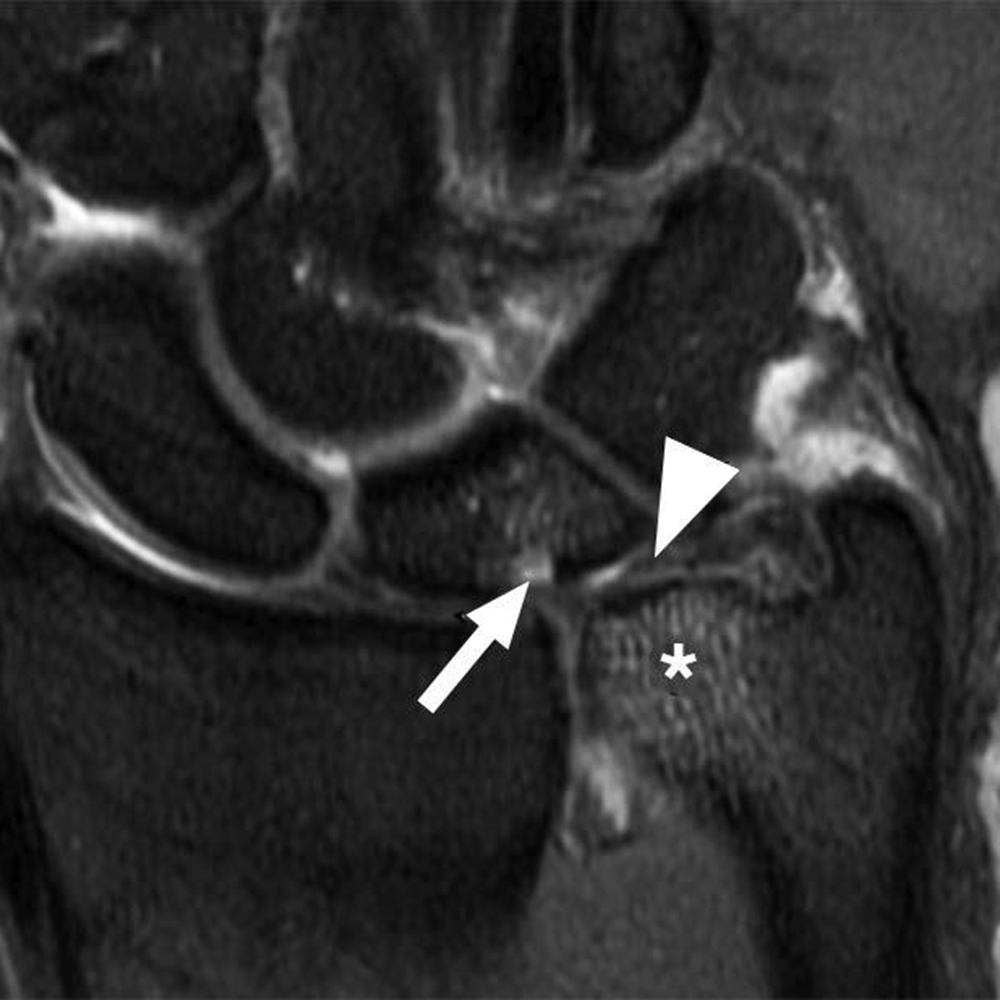

In comparison with acute traumatic injuries to the TFCC, which may affect various components of the complex, chronic ulnar abutment typically causes central degeneration and perforation of the triangular fibrocartilage disk proper, as outlined by the Palmer classification. The spectrum of progressive pathologic changes in ulnar abutment includes degenerative tearing of the TFCC, ulnar-sided chondromalacia, tears of the lunotriquetral ligament, and lunotriquetral instability—and, in advanced stages, osteoarthritis of the distal radioulnar joint and ulnar side of the radiocarpal compartment. The typical areas of cartilage loss and associated reactive marrow changes are localized to the ulnar head, ulnar side of the proximal aspect of the lunate, and radial side of the proximal aspect of the triquetrum (Fig. 1).

Radiography provides the most accurate determination of the ulnar variance and cannot be substituted with other imaging modalities, particularly in the detection of subtle changes that can be determined only by standard radiographic positioning. MRI provides detailed assessment of the TFCC, bone, and articular cartilage. MRI and CT arthrography can be used to determine the integrity of the TFCC and lunotriquetral ligament.